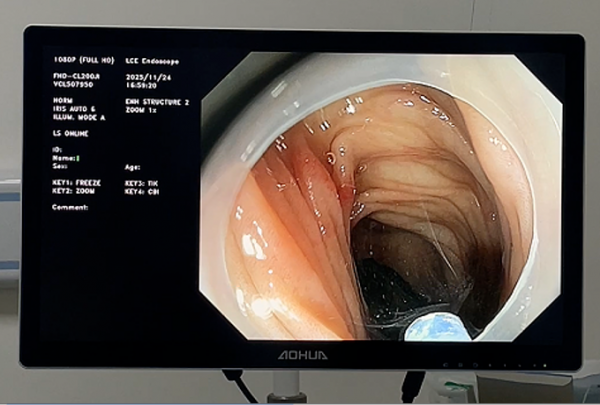

术中,张俊伟主任凭借娴熟的操作技巧,在胃镜直视下精准定位钢笔帽,利用网篮轻柔包裹异物,缓慢将其拖出。整个手术过程仅耗时15分钟,异物完整取出,患儿生命体征平稳,未出现任何不良反应。